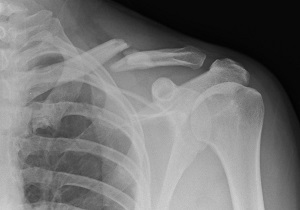

روشی جدید برای درمان شکستگی استخوان با استفاده از جدیدترین فناوری های روز دنیا را ببینید.